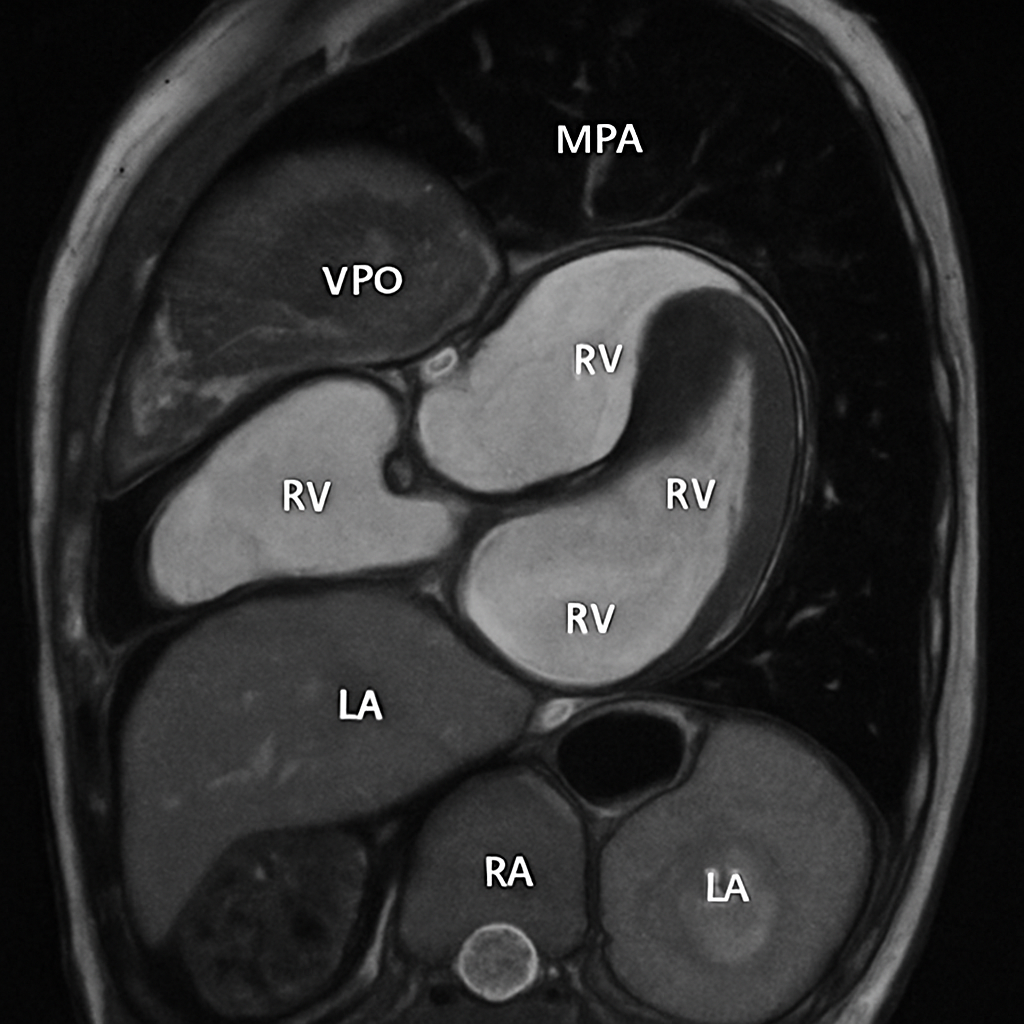

MRI — Four-Chamber View

Cardiac MRI four-chamber (4CH) long-axis view showing all four chambers, both AV valves (mitral and tricuspid), interventricular and interatrial septa. SSFP bright-blood.

MRI AI Generated 2026-03-16

Ssfp Four Chamber

bSSFP cine, four-chamber view. Show all chambers, AV valves, septa. Bright blood.

OpenAI gpt-image-1